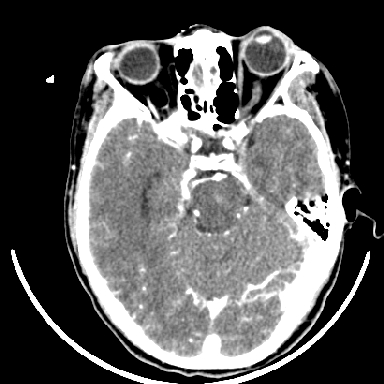

支持右侧基底节区(主要为外囊区)原发性脑出血。

支持右侧基底节区(主要为外囊区)原发性脑出血----有无血管畸形及动脉瘤或说出血原因待查

但脑出血早期做增强是不是有点太冒险了?